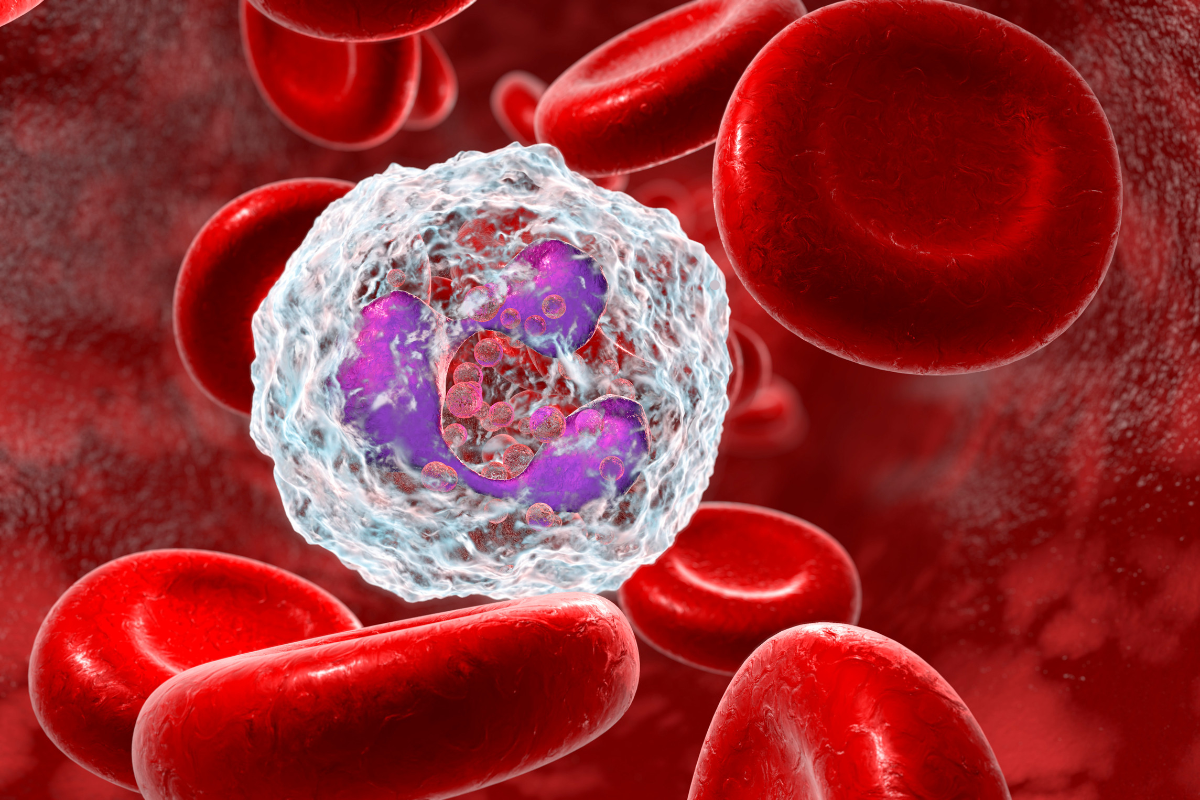

Il C60, un antiossidante molto efficace, neutralizza i radicali liberi, protegge il DNA, ottimizza i mitocondri e rallenta il processo di invecchiamento. Un ampio studio ha dimostrato che il C60 disciolto in olio d’oliva può raddoppiare la durata di vita dei ratti.

Scoprite come questa molecola rivoluzionaria aumenta l’energia cellulare, migliora la memoria, potenzia l’immunità e prolunga l’aspettativa di vita: il segreto anti-invecchiamento definitivo è finalmente svelato! 🚀